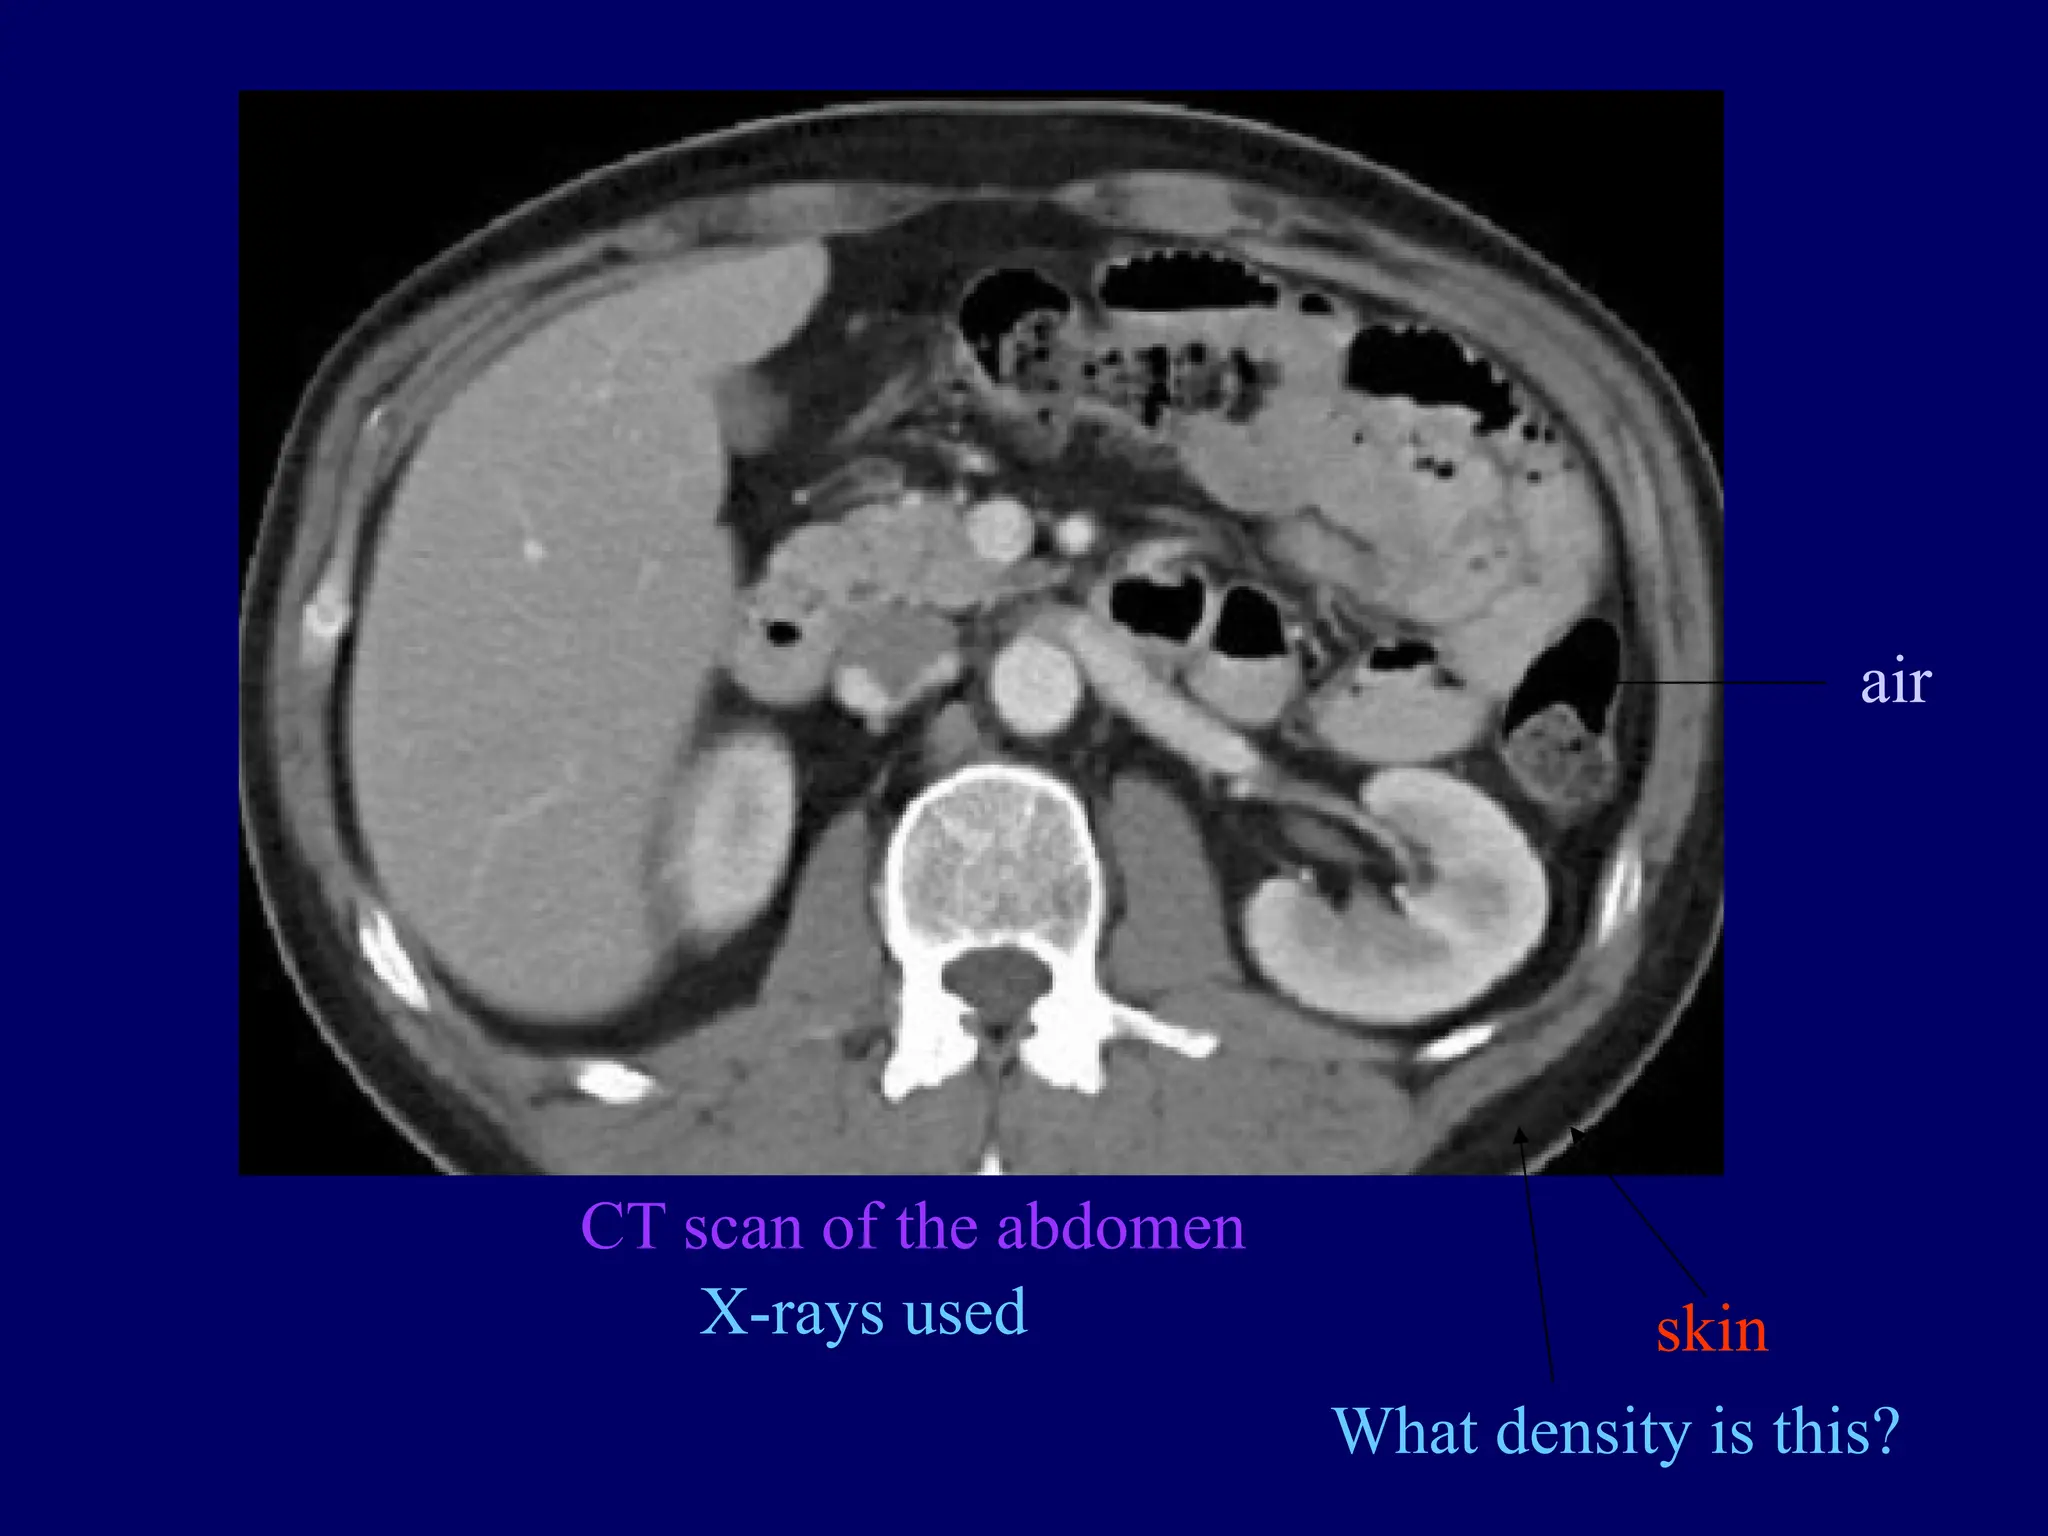

CT scan of the abdomen

X-rays used skin

What density is this?

air

CT scan ofthe abdomen X-rays used skin What density is this? air